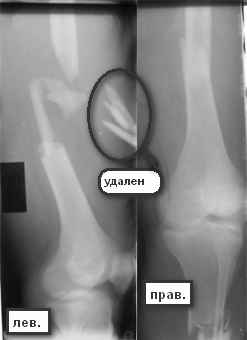

Вчера сделали снимки - положение отломков и осколков вот такое. На перевязке: из раны небольшое кол-во сгустков крови с примесью гноя , хотя бедро спокойное, гипертермии ни локальной ни общей нет. Вопрос: как быть дальше? открывать рану, "чистить" ее, наладить ее перфузию АС, АБ? что делать с осколками, попробовать перекрыть область перелома с фиксацией основных отломков аппаратом. Или осколки убрать и состыковать основные отломки с жутким укорочением и большими проблемами при зашивании раны?

Свободные костные отломки, несвязанные с живыми мягкими тканями в условиях инфицированного перелома, необходимо удалить.

Добрый вечер,коллеги! На мой взгляд по описанной картине имеется остеомиелит ,увы :( . Мне кажется ,что стоит убрать нежизнеспособные осколки , помыть , поставить спейсер с антибиотиком после рассверливания канала , сохранив (или попытаться сохранить ) длину и ось бедра , а после санации гнойного процесса дальше решать проблемы .